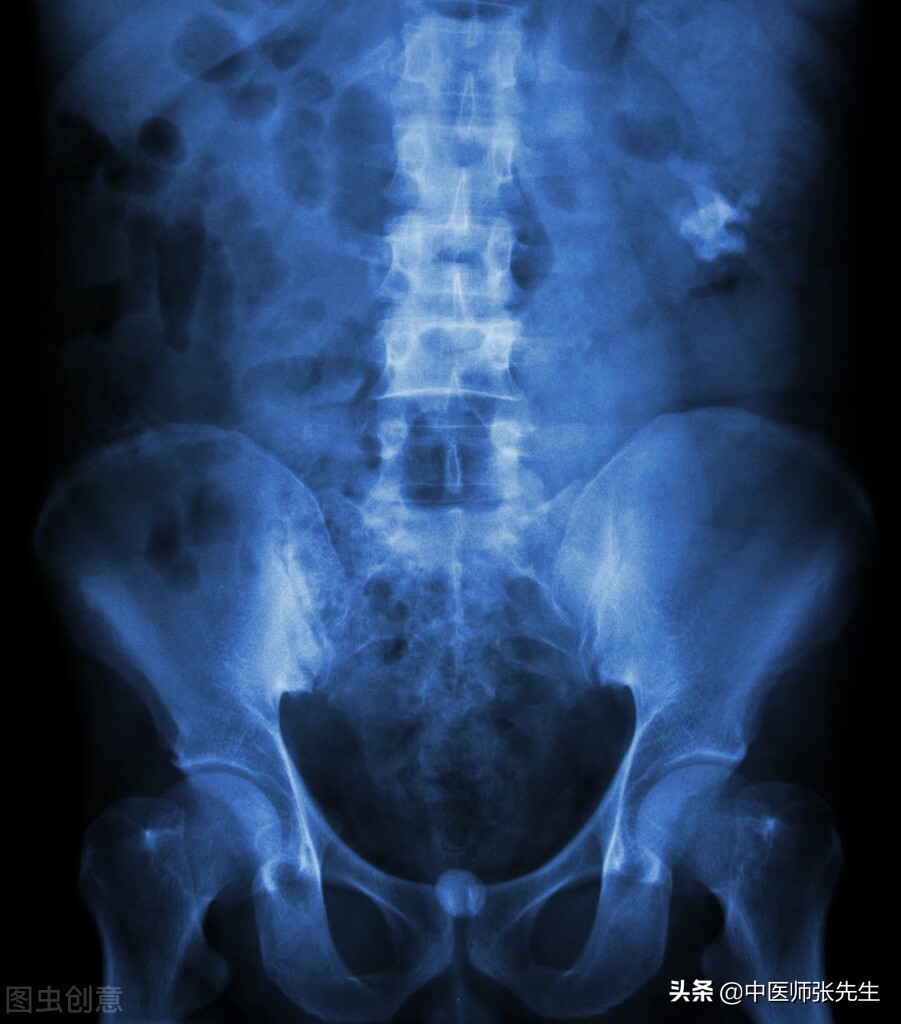

肾结石的主要症状即尿中时常夹杂砂石,小便涩痛;或排尿时突然中断;或腰痛剧烈沿小腹向会阴方向放散;或尿道窘迫疼痛,尿中带血。肾气不充,气化不利,是形成结石的主要内在因素,而结石形成后,气血淤滞逐渐转为矛盾的主要方面,结石内阻,久留不去,必然会导致气血阻滞,膀胱气化不宣而愈甚的病理机制,所以气机淤滞是肾结石的主要病理机制。因此,治疗肾结石要两者兼顾,既要行气利尿排石通淋,又要打通经络,祛淤热、通阻滞。

肾结石患者,在绞痛发作之时,湿热蕴结之象表现最为突出。此时,因湿热淤结,结石阻塞,影响血脉运行,肾与膀胱化气功能低下,欲排又不能,气机因之淤滞,升不得升,降不得降,络道梗阻不通,故发生绞痛症状。这种绞痛的发作,是邪正相争的客观反映,也是体内结石移动的征兆,因此,及时因势利导,采用清热利湿,行气活血,通淋化石药物治疗,解决邪正相持的情况,恢复机体有效的化气功能,则常能起到使结石由“静”变“动”,获得加速排石的效果。